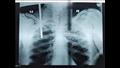

نجح فريق طبي بمستشفى الطوارئ بجامعة طنطا فى استخراج سيخ حديدي من جسم عامل اخترق جسده من جهة اليمين بين الكتف والرأس واستقر بصدره إثر سقوطه عليه أثناء تأدية عمله بإحدى شركات المقاولات.

أوضح الدكتور محمد حنتيرة القائم بعمل عميد كلية الطب جامعة طنطا ورئيس مجلس إدارة المستشفيات الجامعية أنه فور استقبال الحالة تم استدعاء الفريق الطبي المتكامل المشكل من كافة التخصصات الجراحية المعنية بمثل تلك الحالات وتوفير كافة التجهيزات الطبية اللازمة، موضحًا أنه تم إجراء الجراحة اللازمة للمريض وتقديم الرعاية الطبية له بعد خروجه من الجراحة مشيرًا إلى استقرار حالته بالعناية المركزة الجراحية بمستشفى الطوارئ.

أوضح الدكتور حسن التطاوي المدير التنفيذي لمستشفيات جامعة طنطا أن الجراحة استغرقت 5 ساعات وأن الفريق الطبى يضم كل من الدكتور محمد العيسوى المدرس بقسم جراحة الأوعية الدموية والدكتور محمد حسن عبد العاطي المدرس المساعد بقسم جراحة الأوعية الدموية ، والدكتور أحمد بدوى المدرس المساعد بقسم جراحة الأوعية الدموية، والدكتور شريف طارق الطبيب المقيم بذات القسم، ومن قسم جراحة القلب والصدر الدكتور محمد الجاريه المدرس بالقسم، والدكتورة سمر محمد المدرس المساعد بذات القسم، ومن قسم التخدير الدكتورة فاطمة السماحى المدرس المساعد، والدكتور أحمد البرادعى الطبيب المقيم، وكان في استقبال الحالة الدكتور أحمد النواجي المدرس المساعد بقسم الطوارىء.